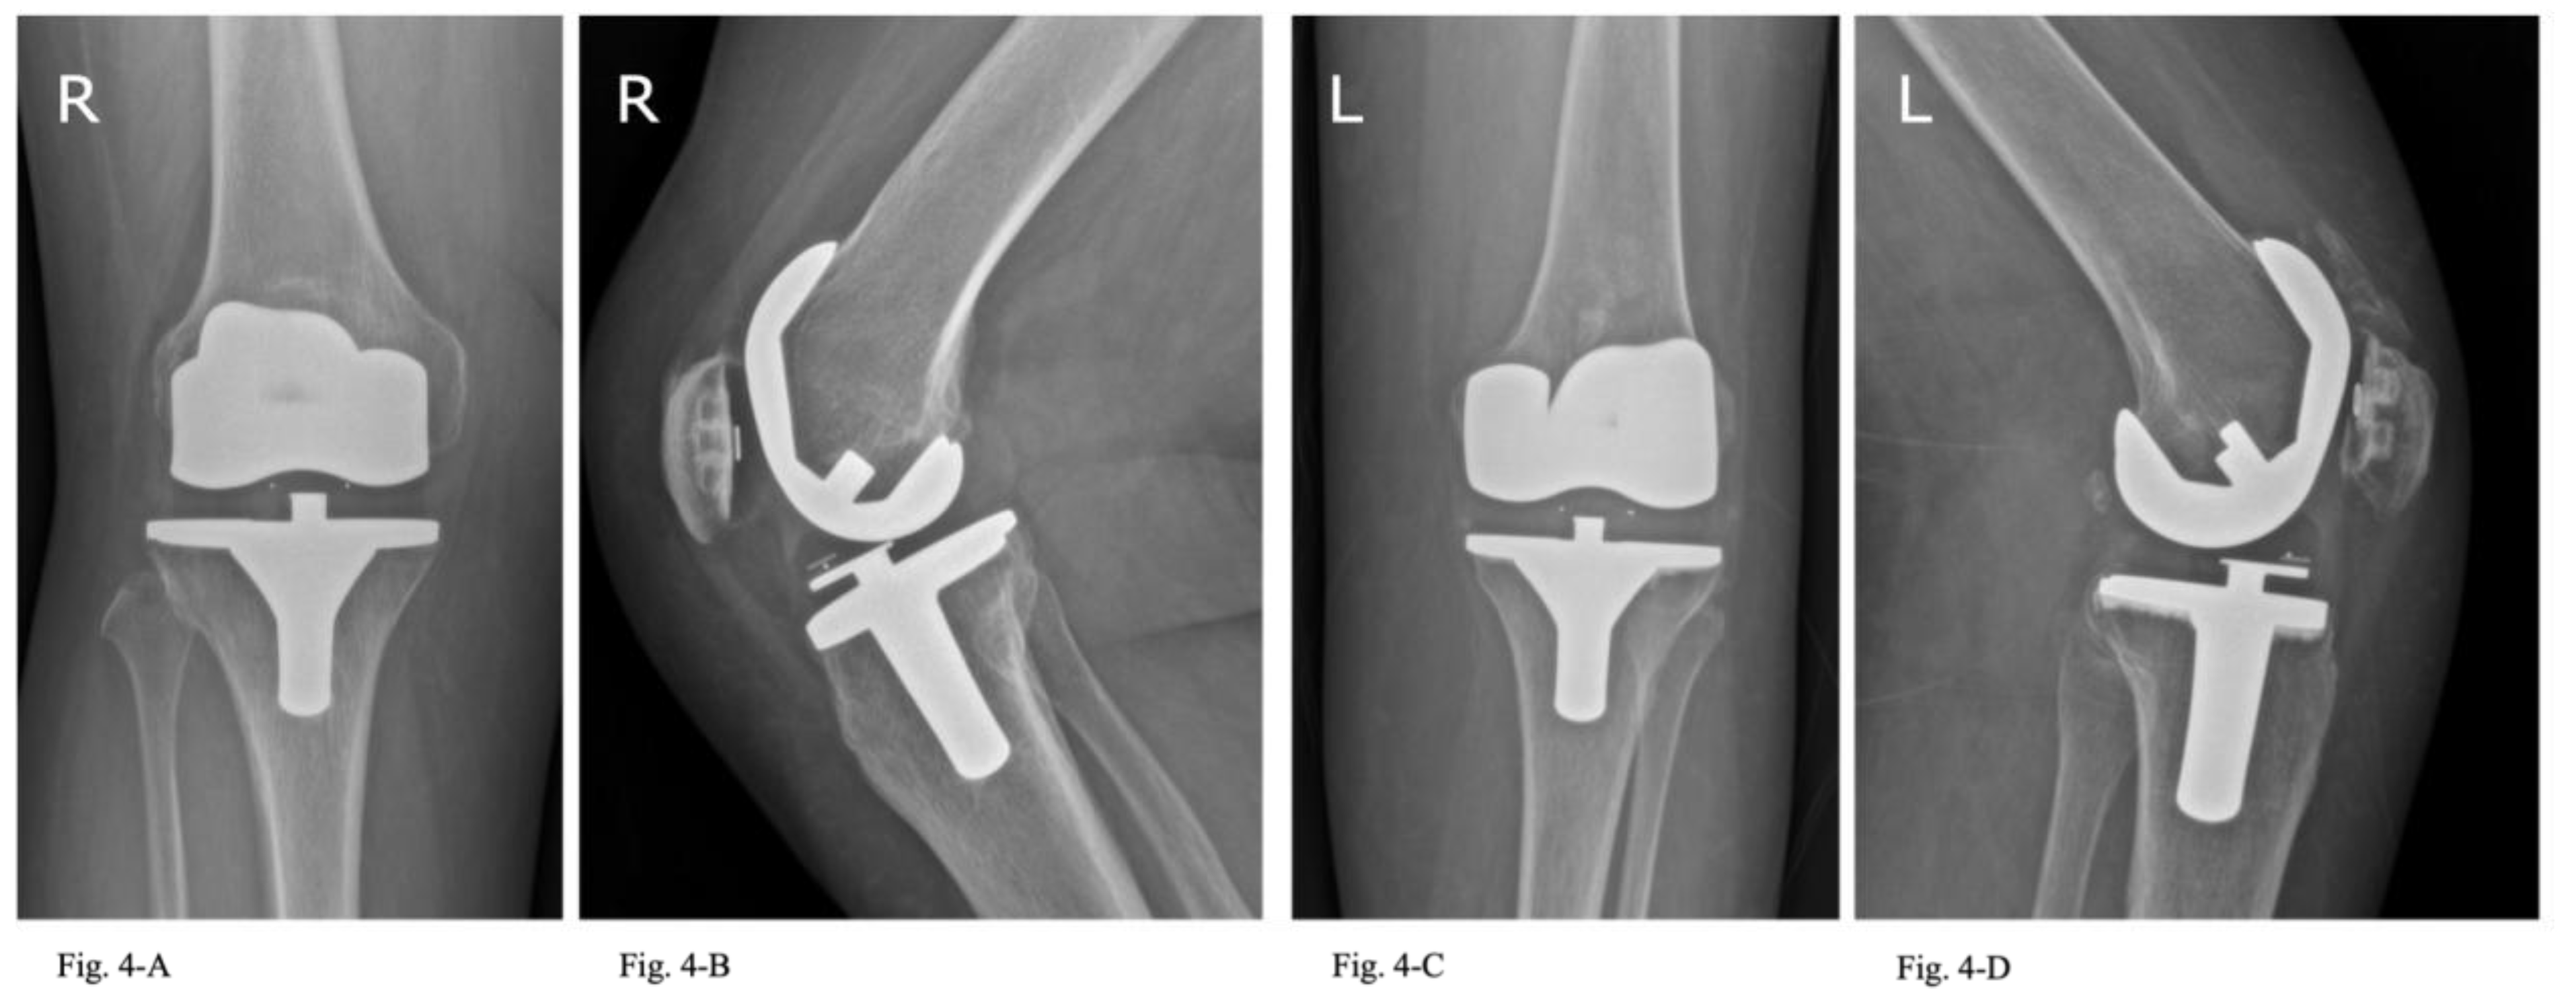

In the radiological evaluation, no evidence of osteolysis was detected in either group. Radiolucent lines between 1-2 mm were found in 3 TKAs of 2 patients in the cementless group, but none in the hybrid cemented group. However, there was no significant difference (p = 0.075) in the incidence of loosening between the two techniques at a minimum follow-up of 10 years (Figure 4).

Radiological outcomes further support the equivalence of these fixation methods. Radiolucent lines were observed in three tibial components in the cementless group, whereas none were found in the hybrid cemented group. These radiolucencies were non-progressive, did not correlate with implant failure or clinical symptoms, and the difference between groups was not statistically significant (p = 0.075). As reported by Costales et al. [25], radiolucent lines are a common occurrence after cementless TKA.

Figure 4. Anteroposterior and lateral radiographs of cementless (Fig. 4-A–B) and hybrid cemented (Fig. 4-C–D) TKA implants, 10 years postoperatively.